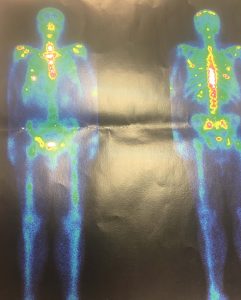

Ο ολόσωμος ραδιοϊσοτοπικός έλεγχος δια ραδιοϊσοτόπων Tc-99 MDP και γ-camera και τριών φάσεων (Εικόνα 1) έδειξε την ύπαρξη πολλαπλών εστιών αυξημένης συγκέντρωσης του ραδιοφαρμάκου στο κρανίο, στο στέρνο, τις πλευρές, στη Σπονδυλική Στήλη, στα οστά της λεκάνης, συμβατές με πολλαπλές δευτεροπαθείς εντοπίσεις.

Εικόνα 1 – Ραδιοϊσότοπα